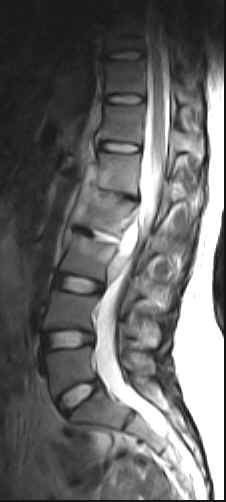

The L1, L2 and L3 vertebral bodies show hypointense areas on the T1W images and these turn hyperintense on the T2W images. The L1-L2 and L2-L3 intervertebral discs are also involved. There is an anterior epidural lesion at the L2 and L3 vertebral levels. It is hypointense with a hyperintense rim on the T1W images and hyperintense with a hypointense rim on the T2W images. This would be suggestive of an abscess. Slight prevertebral soft tissue extension is noted. The psoas muscles are bulky bilaterally and show presence of abscesses. A similar lesion is noted within the left paraspinal muscles.

·                     There is replacement of the normal marrow by inflammatory tissue (with hyperemia, edema and pus) and this is usually hypointense on the T1W images and turns hyperintense on the T2W images. It may be found in the subchondral region or may be seen as a more diffuse involvement. The sagittal images may show it to be a disc centered process. Contrast enhancement is useful in those who have an inhomogeneous marrow pattern and is of marginal value in those with fatty vertebral marrow. Fat saturation techniques help. Typically the hyperemic and osteomyelitic bone enhances. Skip lesions  may be seen with multivertebral involvement and relative sparing of the intervertebral discs. Involvement of the posterior elements is fairly common.

·                     In people over thirty years an intranuclear cleft (hypointense linear signal on the T2W images) is noted within the centre of the disc. The loss of this cleft on T2W images may suggest early discitis (especially when the cleft is well visualized within the other discs). The disc may be decreased in height and hyperintense on the T2W images. Occasionally an enlarged edematous disc may be encountered. Adjacent marrow signal changes and erosion of the cortical endplates may be seen. The involved disc has a very variable pattern of enhancement. Initially thin central linear or thick focal enhancement conforming to the signal alteration on the T2W images may be seen. Thin or thick marginal disc enhancement may be noted. Occasionally the disc enhances inspite of there being no signal alteration.

·                     Tuberculosis tends to involve the soft tissues commonly with abscess formation. Large paravertebral or psoas abscesses (calcifications may be seen) are commonly involved. These may be out of proportion to the degree of involvement of the vertebra or disc. Abscesses may also be seen in the paraspinal region and epidural space. The abscesses are usually located ventrally in the cervical and lumbar spine and posteriorly in the dorsal spine. The leptomeninges may be involved. Intraosseus abscesses may be seen. The abscesses are invariably seen to have a centre which is isointense to hypointense to normal muscle with a slightly hyperintense rim on the T1W images. On the T2W images the centre is hyperintense and the rim hypointense. Contrast enhancement of the rim is noted. These lesions usually yield drainable pus. It may be difficult to distinguish phlegmon (inflammatory mass of granulation tissue) from an abscess. Phlegmon usually shows diffuse contrast enhancement. This inflammatory tissue may tunnel beneath the paraspinous ligaments.

·                     The end-stage shows narrowing of the disc space or partial or complete obliteration with fusion of the vertebral bodies. The soft tissue components usually regress. The vertebral body may show central or anterior wedging with gibbus formation. Hyperintense signal on the T1W images may reflect the presence of fatty changes or yellow marrow, the result of healing. Sclerotic changes (hypointense) may be seen.